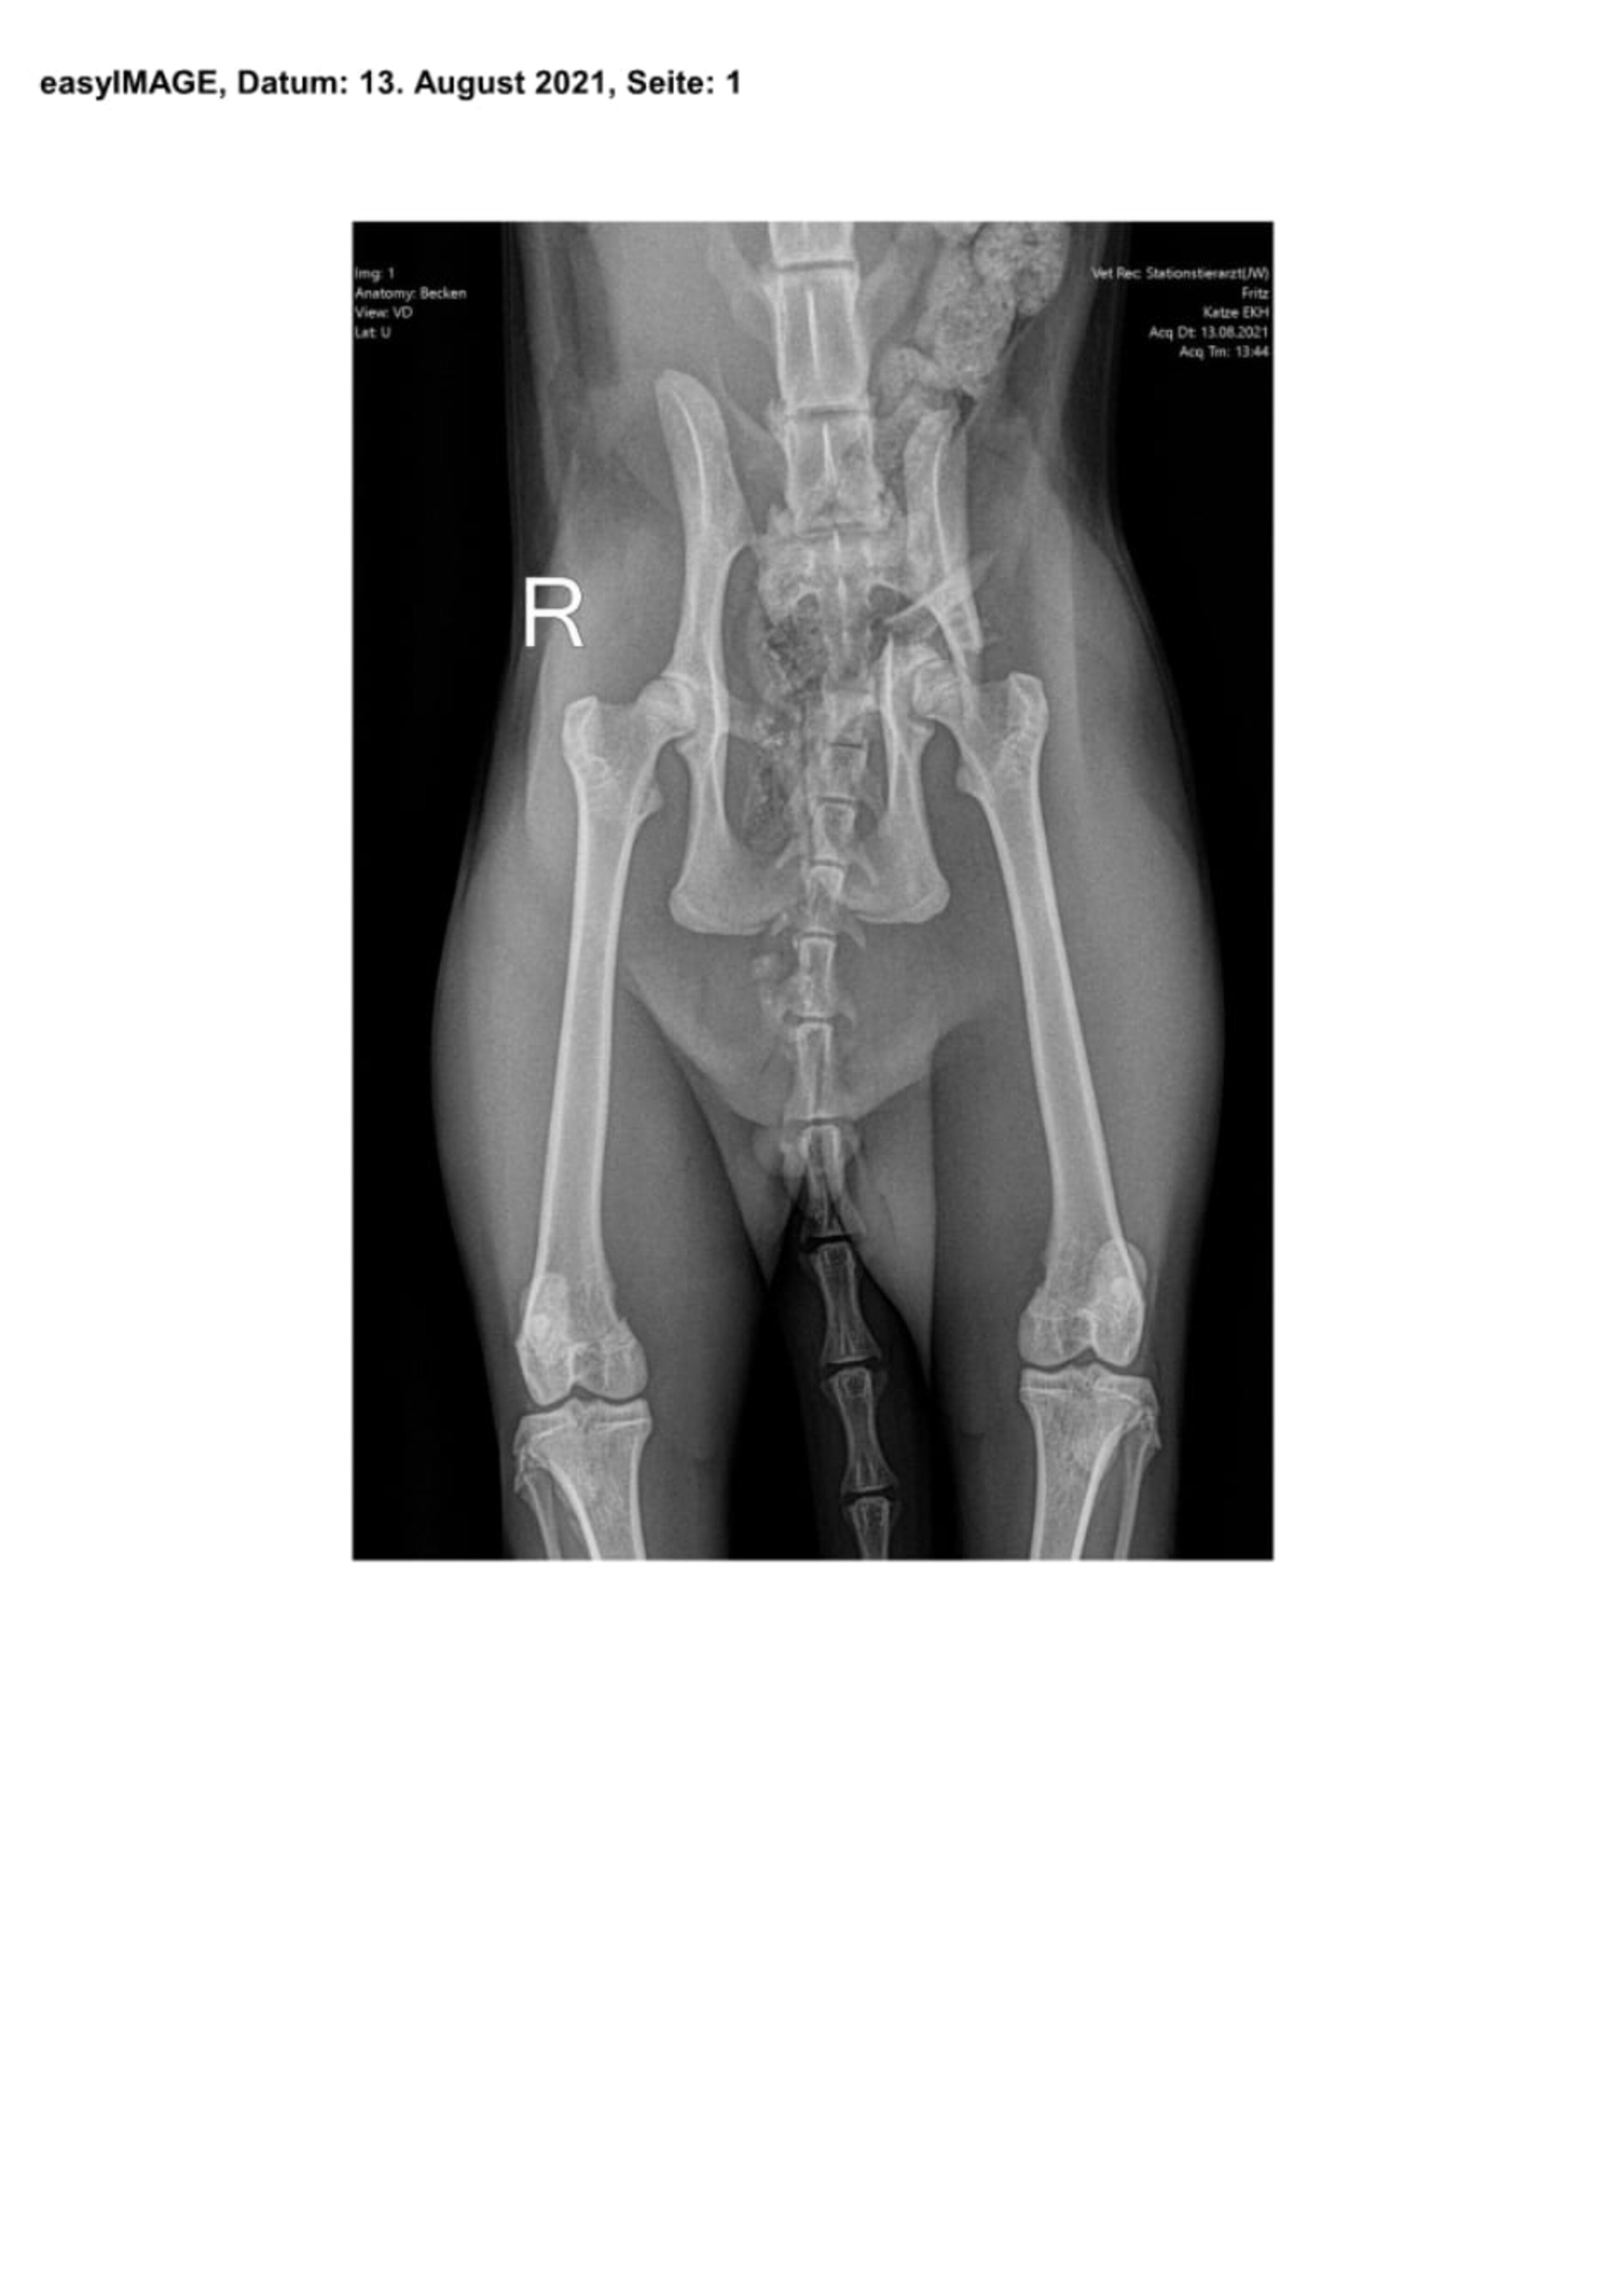

Am Abend des 8. August 2021 kam Fritz nicht nach Hause. Gegen 19 Uhr erreichte mich der Anruf von einem Tierarzt, der mir mitteilte, dass Fritz schwerverletzt bei ihm abgegeben worden sei und es ihm nicht gut gehe. Unser junger, roter Kater Fritz war vermutlich angefahren worden und konnte seine Hinterläufe nicht mehr bewegen. Wir brachten ihn sofort nach Weilheim in die Tierklinik, wo das erste Röntgenbild einen beidseitigen Bruch des Beckens zeigte. Fritz wurde stationär aufgenommen und mehrere Tage intensiv behandelt, bevor er operiert werden konnte. Nach der Entlassung aus der Klinik folgten sechs Wochen Bewegungseinschränkung in einem Käfig. Er durfte sich weder im Haus noch im Garten frei bewegen. Danach blieb ihm der Freigang in der Natur noch für weitere vier Wochen versagt. Fritz war sehr geduldig und so brav, seine Katzenfreundinnen Mona und Lisa leisteten ihm Gesellschaft. Unsere Streicheleinheiten waren unzählbar... Die Operationswunden sind sehr gut verheilt, die Verletzungen machen keine Probleme mehr. Der junge Fritz ist wieder „ganz der alte“ und erfreut sich eines wundervollen Katzenlebens!

Bei der Einlieferung war der Kater in einem schweren Schockzustand, sodass sein Kreislauf zunächst mit Infusionen und Schmerzmedikamenten unter dem Rotlicht stabilisiert werden musste. Nachdem eine leichte Besserung eingetreten war, wurde eine Ultraschalluntersuchung des Bauchraums durchgeführt, um lebensbedrohliche innere Blutungen auszuschließen und ein erstes röntgenologisches Screening in Form von zwei Übersichtsaufnahmen. Dabei stellte sich heraus, dass Fritz neben den schon erwähnten Beckenfrakturen, die häufig mit einem massiven Blutverlust in den Beckenraum einhergehen, auch leichte Lungenverletzungen erlitten hatte. Unter der Schocktherapie besserte sich das Allgemeinbefinden des Patienten innerhalb weniger Tage. In den regelmäßigen Laborkontrollen war jedoch am 11. August eine ausgeprägte Anämie erkennbar, weshalb Fritz noch eine Bluttransfusion erhielt.

Am 13. August, also fünf Tage nach dem Unfall, entschied man sich dann zur Operation, da die Verlaufsuntersuchung dank der wiedergewonnenen Reaktionsfähigkeit des Patienten jetzt den Verdacht einer begleitenden Verletzung des rechten Ischias Nerven aufkommen ließ. Durch Vorbiegen einer Knochenplatte an einem Beckenmodell wurde der Eingriff sorgfältig vorbereitet, um die Operationszeit möglichst kurz halten zu können.